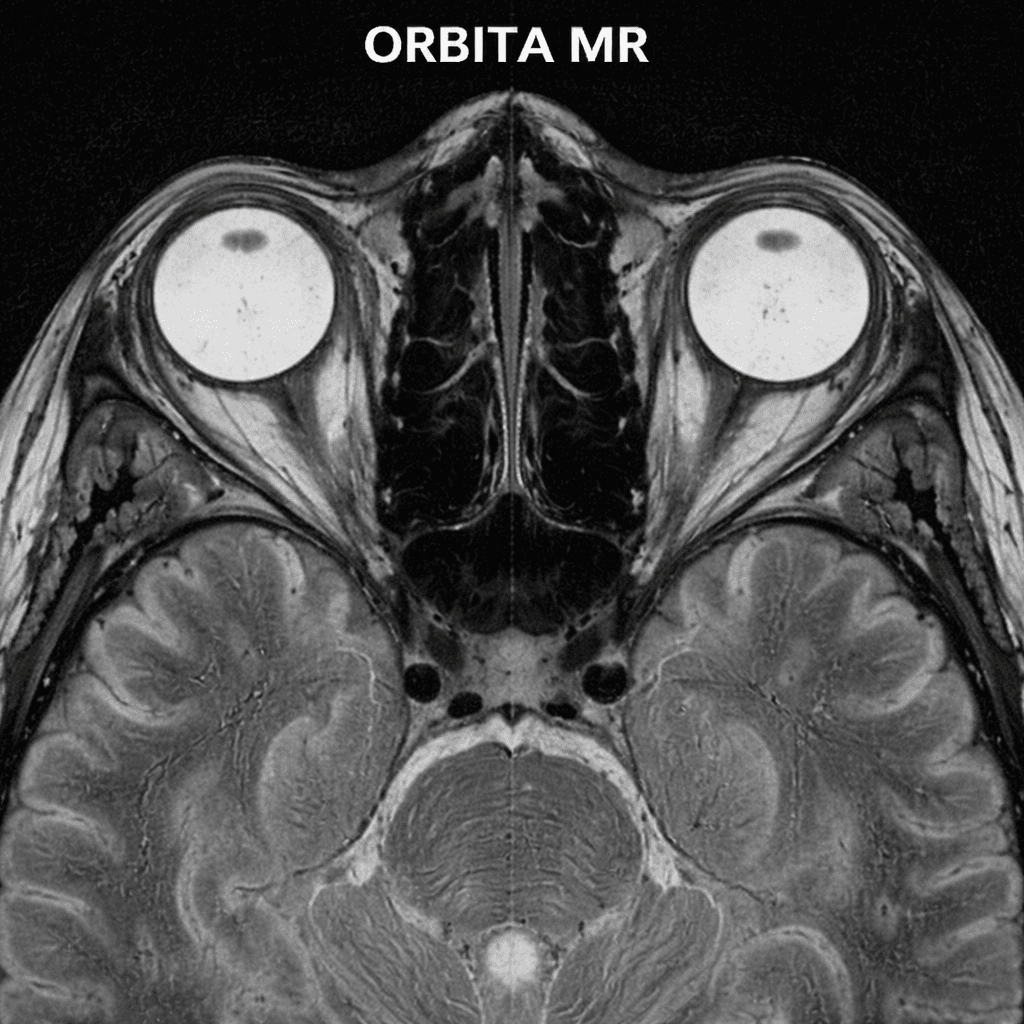

Get superior MR imaging, CT scanning, and radiology services with Orbita MR. Discover check-up packages with a reliable medical imaging center!

Orbita CT Scan: Reliable medical imaging center. High-resolution MRI imaging, fast CT scans, and comprehensive radiology services. Protect your health with our check-up packages!